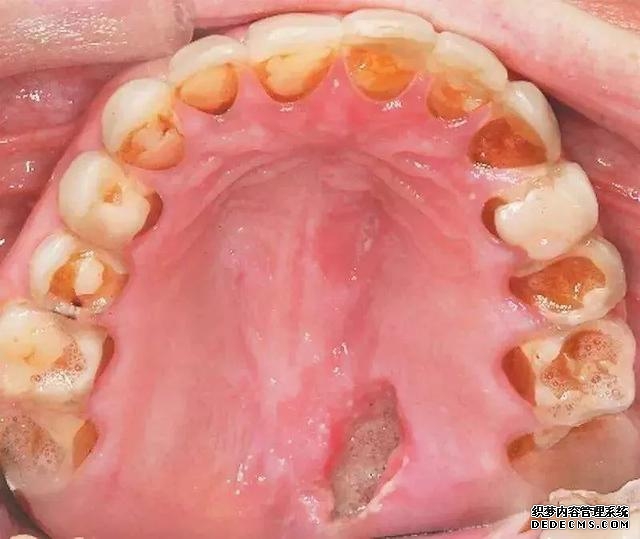

有疼痛感的皮肤、黏膜溃疡,是急性HIV感染的独特症状之一,这种溃疡一般来说比较表浅,边界清楚,基底部是白色的,周围环绕一层薄的红色水肿区域,可出现于口腔黏膜、肛门、阴茎或食道。这种溃疡往往局限在一个部位,反复发作无法痊愈。如果是发生在食道部位的溃疡,患者可能会伴有吞咽疼痛。 虽然溃疡并不能直接诊断HIV感染,但由于HIV主要通过性传播,这些溃疡可能是一些单纯疱疹病毒感染或梅毒引起的。在这些病毒感染在这些疾病的基础上,可能更容易传播HIV,要引起重视。